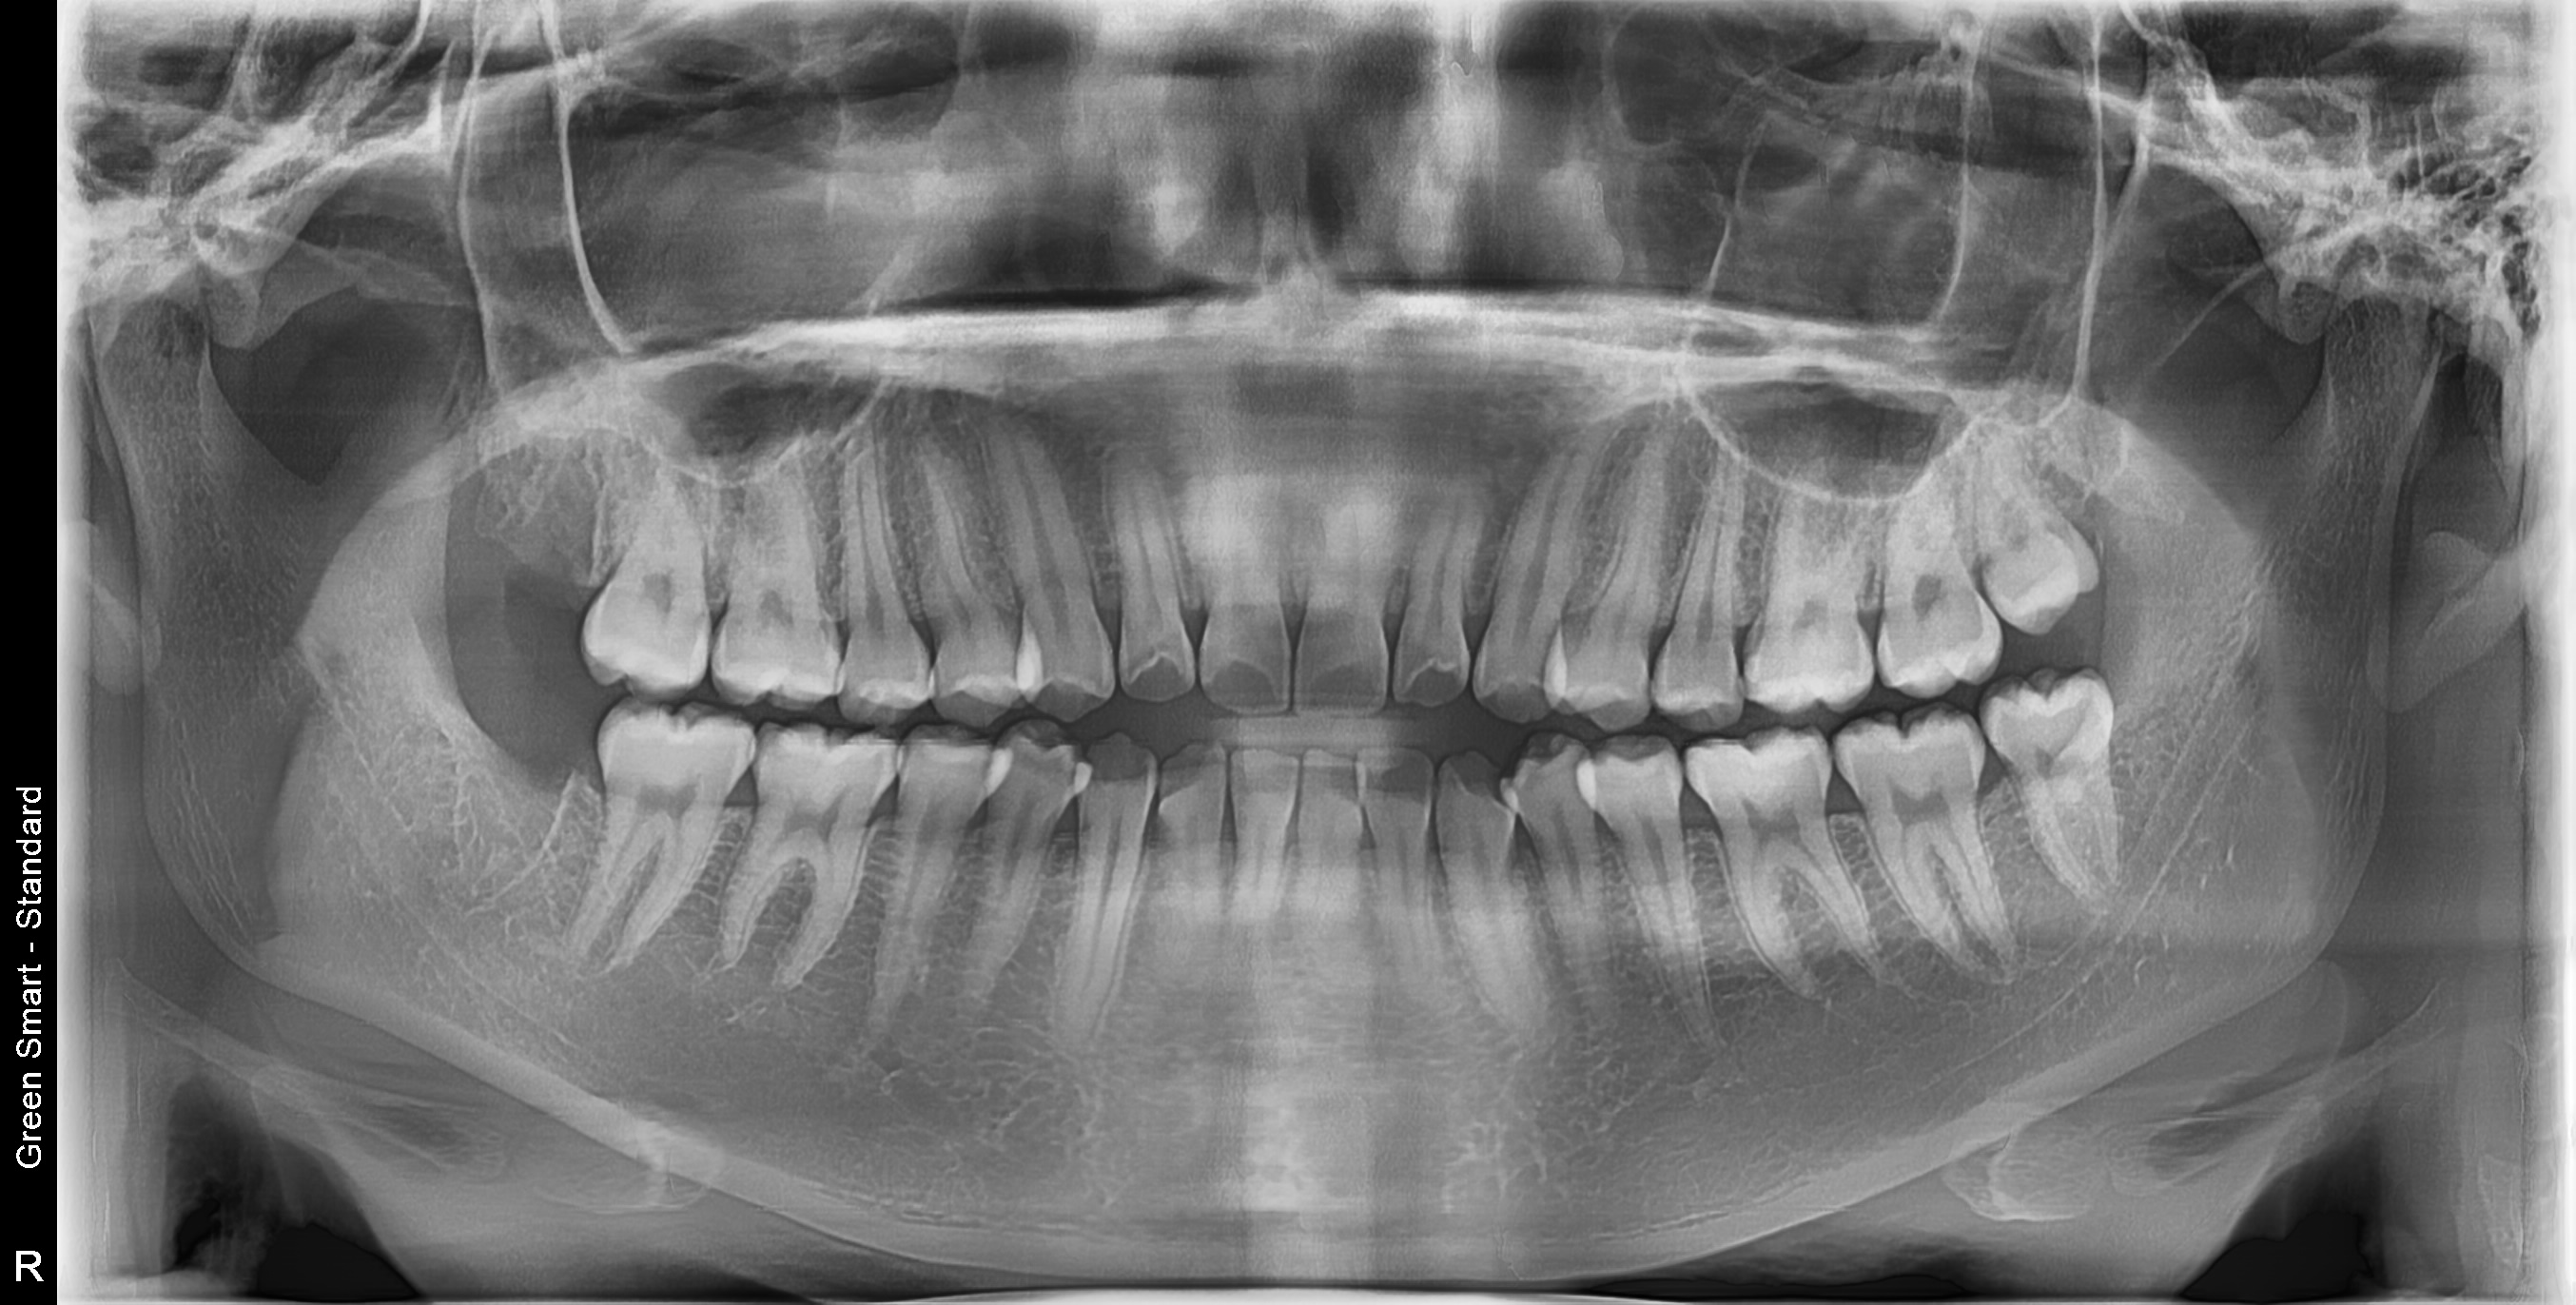

누운 사랑니

옆으로 누워 자라며 옆 치아를 압박할 수 있습니다

중위험

부분매복 사랑니

음식물이 끼기 쉽고 염증이 자주 발생합니다

고위험

완전매복 사랑니

낭종 형성 가능성이 있어 조기 발치가 필요합니다

즉시 처치 필요

수평매복 사랑니

앞 치아를 밀어 치열 불균형과 충치를 유발합니다

복잡한 매복 사랑니 - 잇몸 속 깊이 묻혀있어도 OK

신경 근접 사랑니 - 신경 손상 걱정 없는 안전한 발치

수평 매복 사랑니 - 옆으로 누워있는 어려운 케이스도 가능